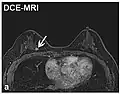

| Dynamic contrast enhanced | DCE | Measures changes over time in the shortening of the spin–lattice relaxation (T1) induced by a gadolinium contrast bolus.[27] | Faster Gd contrast uptake along with other features is suggestive of malignancy (pictured).[28] |

Perfusion weighted

Perfusion-weighted imaging (PWI) is performed by 3 main techniques:

- Dynamic contrast enhanced (DCE): Measuring shortening of the spin–lattice relaxation (T1) induced by a gadolinium contrast bolus.[46]

The acquired data is then postprocessed to obtain perfusion maps with different parameters, such as BV (blood volume), BF (blood flow), MTT (mean transit time) and TTP (time to peak).